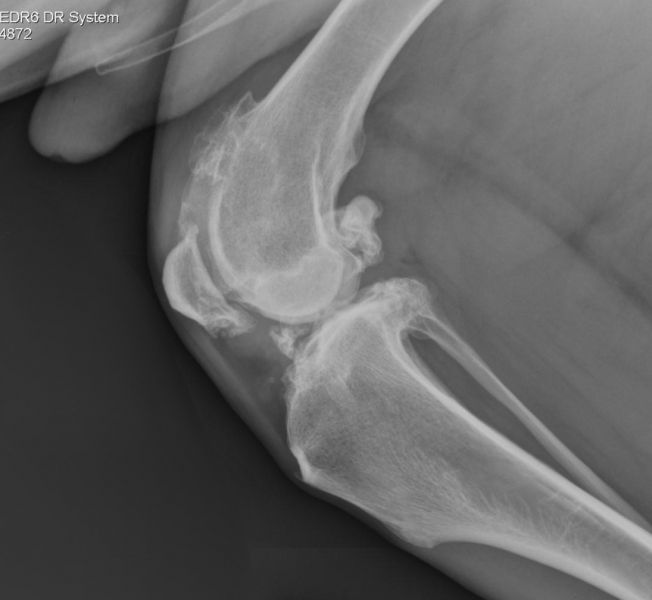

Pets that have radiographic evidence of degenerative joint disease can lead active lifestyles. We own three dogs that are fifteen and one 16-year-old. Even though their x-rays are ugly, they remain active and love to romp around the yard. There is no reason to allow your pet to suffer with untreated pain. For many pets, this may require a multi-modal approach, meaning you may need to keep adding therapies until you achieve the desired effect.